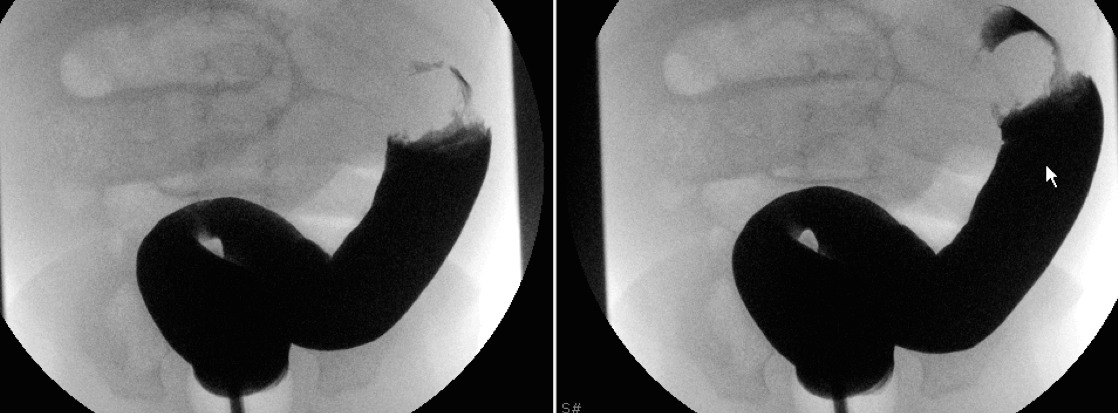

Patients with evidence of bowel perforation require operative intervention. Patients without evidence of bowel perforation are managed with non-operative reduction using hydrostatic (barium, water-soluble contrast or saline) or pneumatic pressure enemas, guided by either fluoroscopy or sonography. Reduction is successful in 80-95% involving ileocolic intussusception with perforation risk of less than 1% for both hydrostatic and pneumatic pressure enemas. The choice of non-operative intervention depends on the radiologist and institution. Before undergoing enema reduction, patients require the following:

- Non-operative reduction is performed using either hydrostatic or pneumatic pressure enemas, guided by fluoroscopy or sonography.